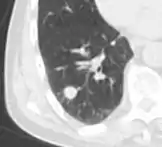

Thin slice and maximal intensity projection of a lung nodule, the latter better visualizing vascular convergence.[9]

• Vascular convergence is where vessels converge to a nodule without adjoining or contacting the edge of the nodule, and is mainly seen in peripheral subsolid lung cancers.[9] It reflects angiogenesis.[9]